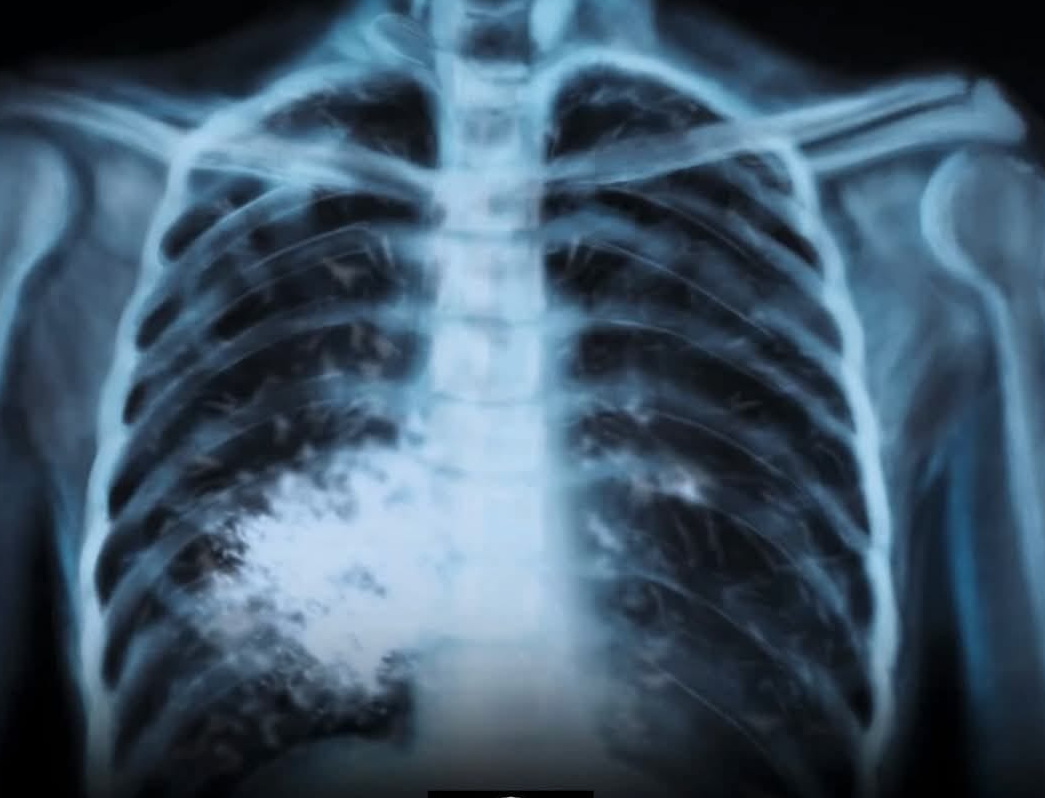

А знаете ли кой е един от най-сериозните рискове, свързани с него? Това е състоянието, наречено „попкорн бял дроб“ – с официалното име облитериращ бронхиолит.

Това е рядко, но необратимо заболяване, което оставя белези по малките дихателни пътища в белите дробове, водещо до постоянна кашлица, хрипове и затруднено дишане.

Наскоро тийнейджър в САЩ, който тайно е пушил електронни цигари в продължение на три години, беше диагностициран с „попкорн бял дроб“ – стряскащо напомняне, че вейпинга съвсем не е безобиден.

Първоначално заболяването е свързано със служители във фабрики за пуканки, изложени на химикала диацетил. Този химикал и негови заместители са открити в някои вейп продукти – особено в нерегламентирани такива.